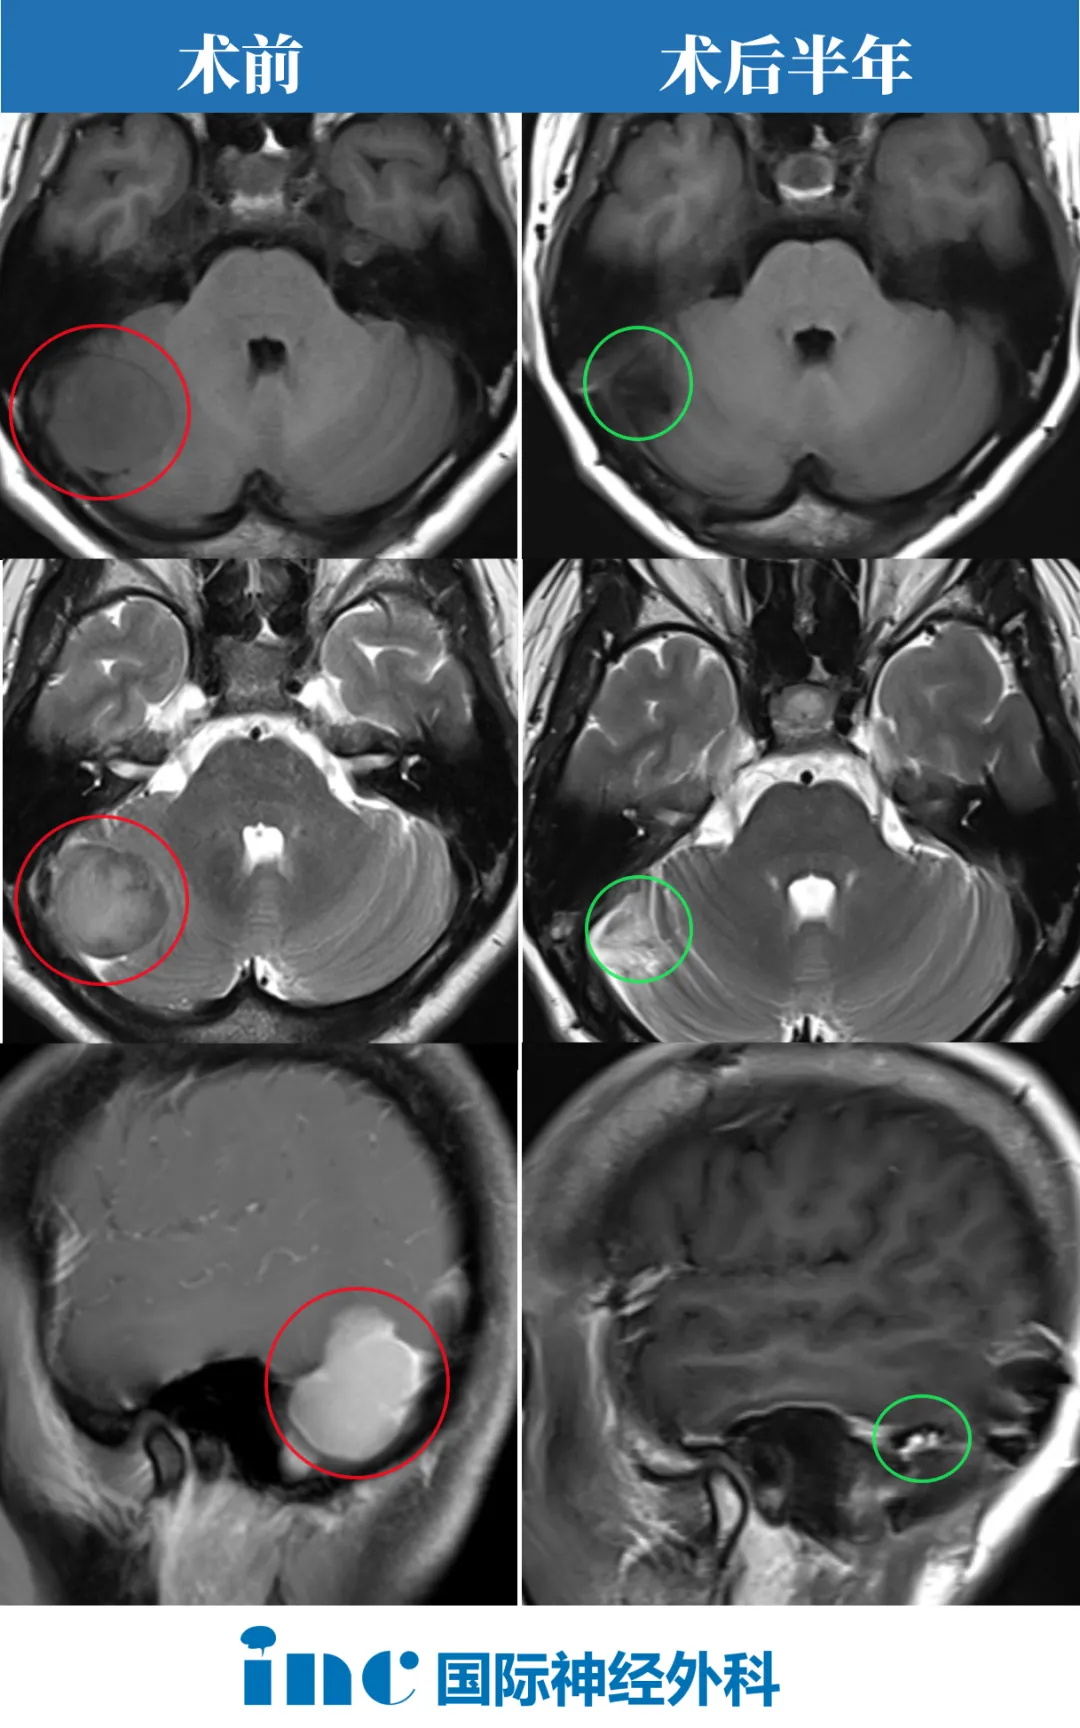

术后半年随访时,巴教授在查看了孙女士影像后回复

“以下是2024年3月22日的MRI截图。他们清楚地记录了肿瘤的完全切除对大脑或周围结构没有负面的副作用。周围的对比增强是由于局部(正常)疤痕形成,剩余的幕也可以看到轻微的增强。肿瘤附着的幕的主要部分被完全切除。这是一个的术后情况。肿瘤的完全切除不仅在术后MRI上可见,而且在天坛医院的手术视频中也有记录。所以,病人不应该担心这个。”